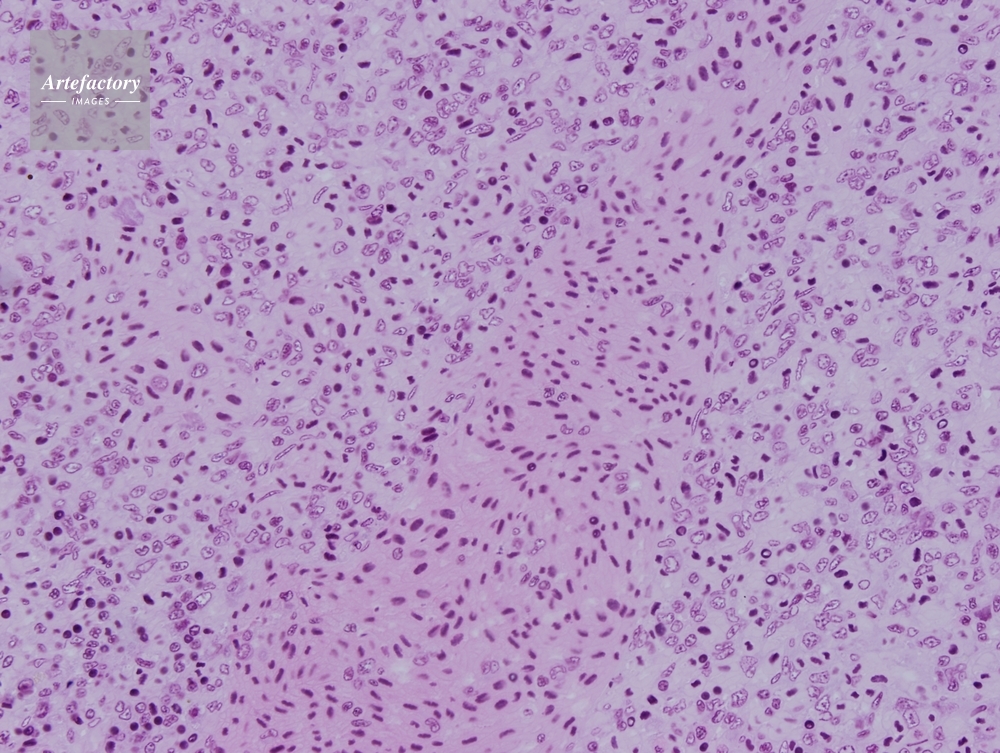

| 作品タイトル | カエル 脾臓 | モデルリリース | なし | |

| 作家 | OLYMPUS CORPORATION Technolab | プロパティリリース | なし | |